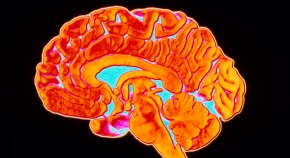

The brain

Sam Falconer

The human brain isn’t much to look at. In the hand, it is a jelly-like mass, easily deformed by touch. But its unassuming appearance belies complex inner workings, many of which are still a mystery to scientists.